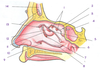

A

Deep temporal nerves

B

Opthalmic nerve (CN V1)

C

Maxillary nerve (CN V2)

D

Pterygopalatine fossa

E

Infra-orbital nerve

F

Posterior superior alveolar nerve

G

Pterygopalatine ganglion

H

Greater and lesser palatine nerves

I

Lateral pterygoid muscle

J

Buccal nerve

K

Lingual nerve

L

Inferior alveolar nerve in mandibular canal

M

Nerve to mylohyoid

N

Chorda tympani

O

Mandibular nerve (CN V3)

P

Auriculotemporal nerve

1

Lacrimal nerve

2

Maxillary nerve

3

Nerve of pterygoid canal

4

Pterygopalatine ganglion

5

Posterior lateral nasal nerves and nasopalatine nerve

6

Greater and lesser palatine nerves

7

Descending paltine artery

8

Superior alveolar nerves

9

Infraorbital nerve

10

Zygomaticofacial nerve

11

Zygomaticotemporal branch

12

Communicating branch

13

Lacrimal gland

14

Zygomatic nerve

15

Pterygopalatine nerves